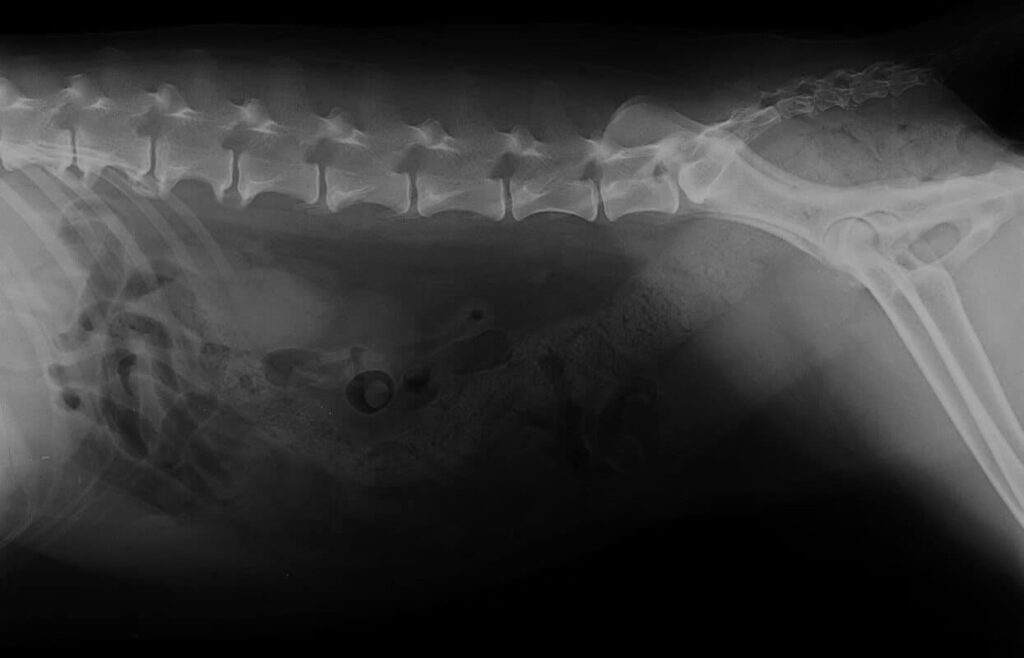

Le « bec de perroquet », scientifiquement connu sous le nom de syndesmophytose ou spondylose déformante, est une pathologie vertébrale caractérisée par la formation d'excroissances osseuses anormales le long de la colonne vertébrale du chien. Contrairement à l'arthrose, avec laquelle elle est souvent confondue, l'origine et le mécanisme de ces formations sont distincts. Alors que l'arthrose affecte principalement les articulations et entraîne la formation d'ostéophytes pour stabiliser une articulation usée, le bec de perroquet est un durcissement progressif du disque intervertébral lui-même. Ce processus mène à la création d'un pont osseux entre les vertèbres, les fusionnant progressivement les unes aux autres. Cette fusion osseuse, qui peut ressembler à la forme recourbée d'un bec de perroquet, réduit considérablement la flexibilité et la mobilité de la colonne vertébrale, pouvant aller jusqu'à former une véritable « colonne de bambou » dans les cas les plus avancés. Cette rigidité est souvent la cause de crises inflammatoires aiguës, générant douleurs et inconfort pour l'animal.

Si vous observez ces symptômes chez votre chien, une consultation vétérinaire s'impose. Seule une radiographie permettra de confirmer le diagnostic de bec de perroquet et d'exclure d'autres pathologies vertébrales, comme une hernie discale, qui nécessitent des approches thérapeutiques différentes.